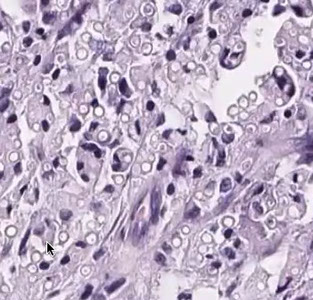

Micro: "dilapidated brick wall" appearance of acantholysis

- also see acanthosis

- pinkish halo surrounds nuclei

Hailey-Hailey disease